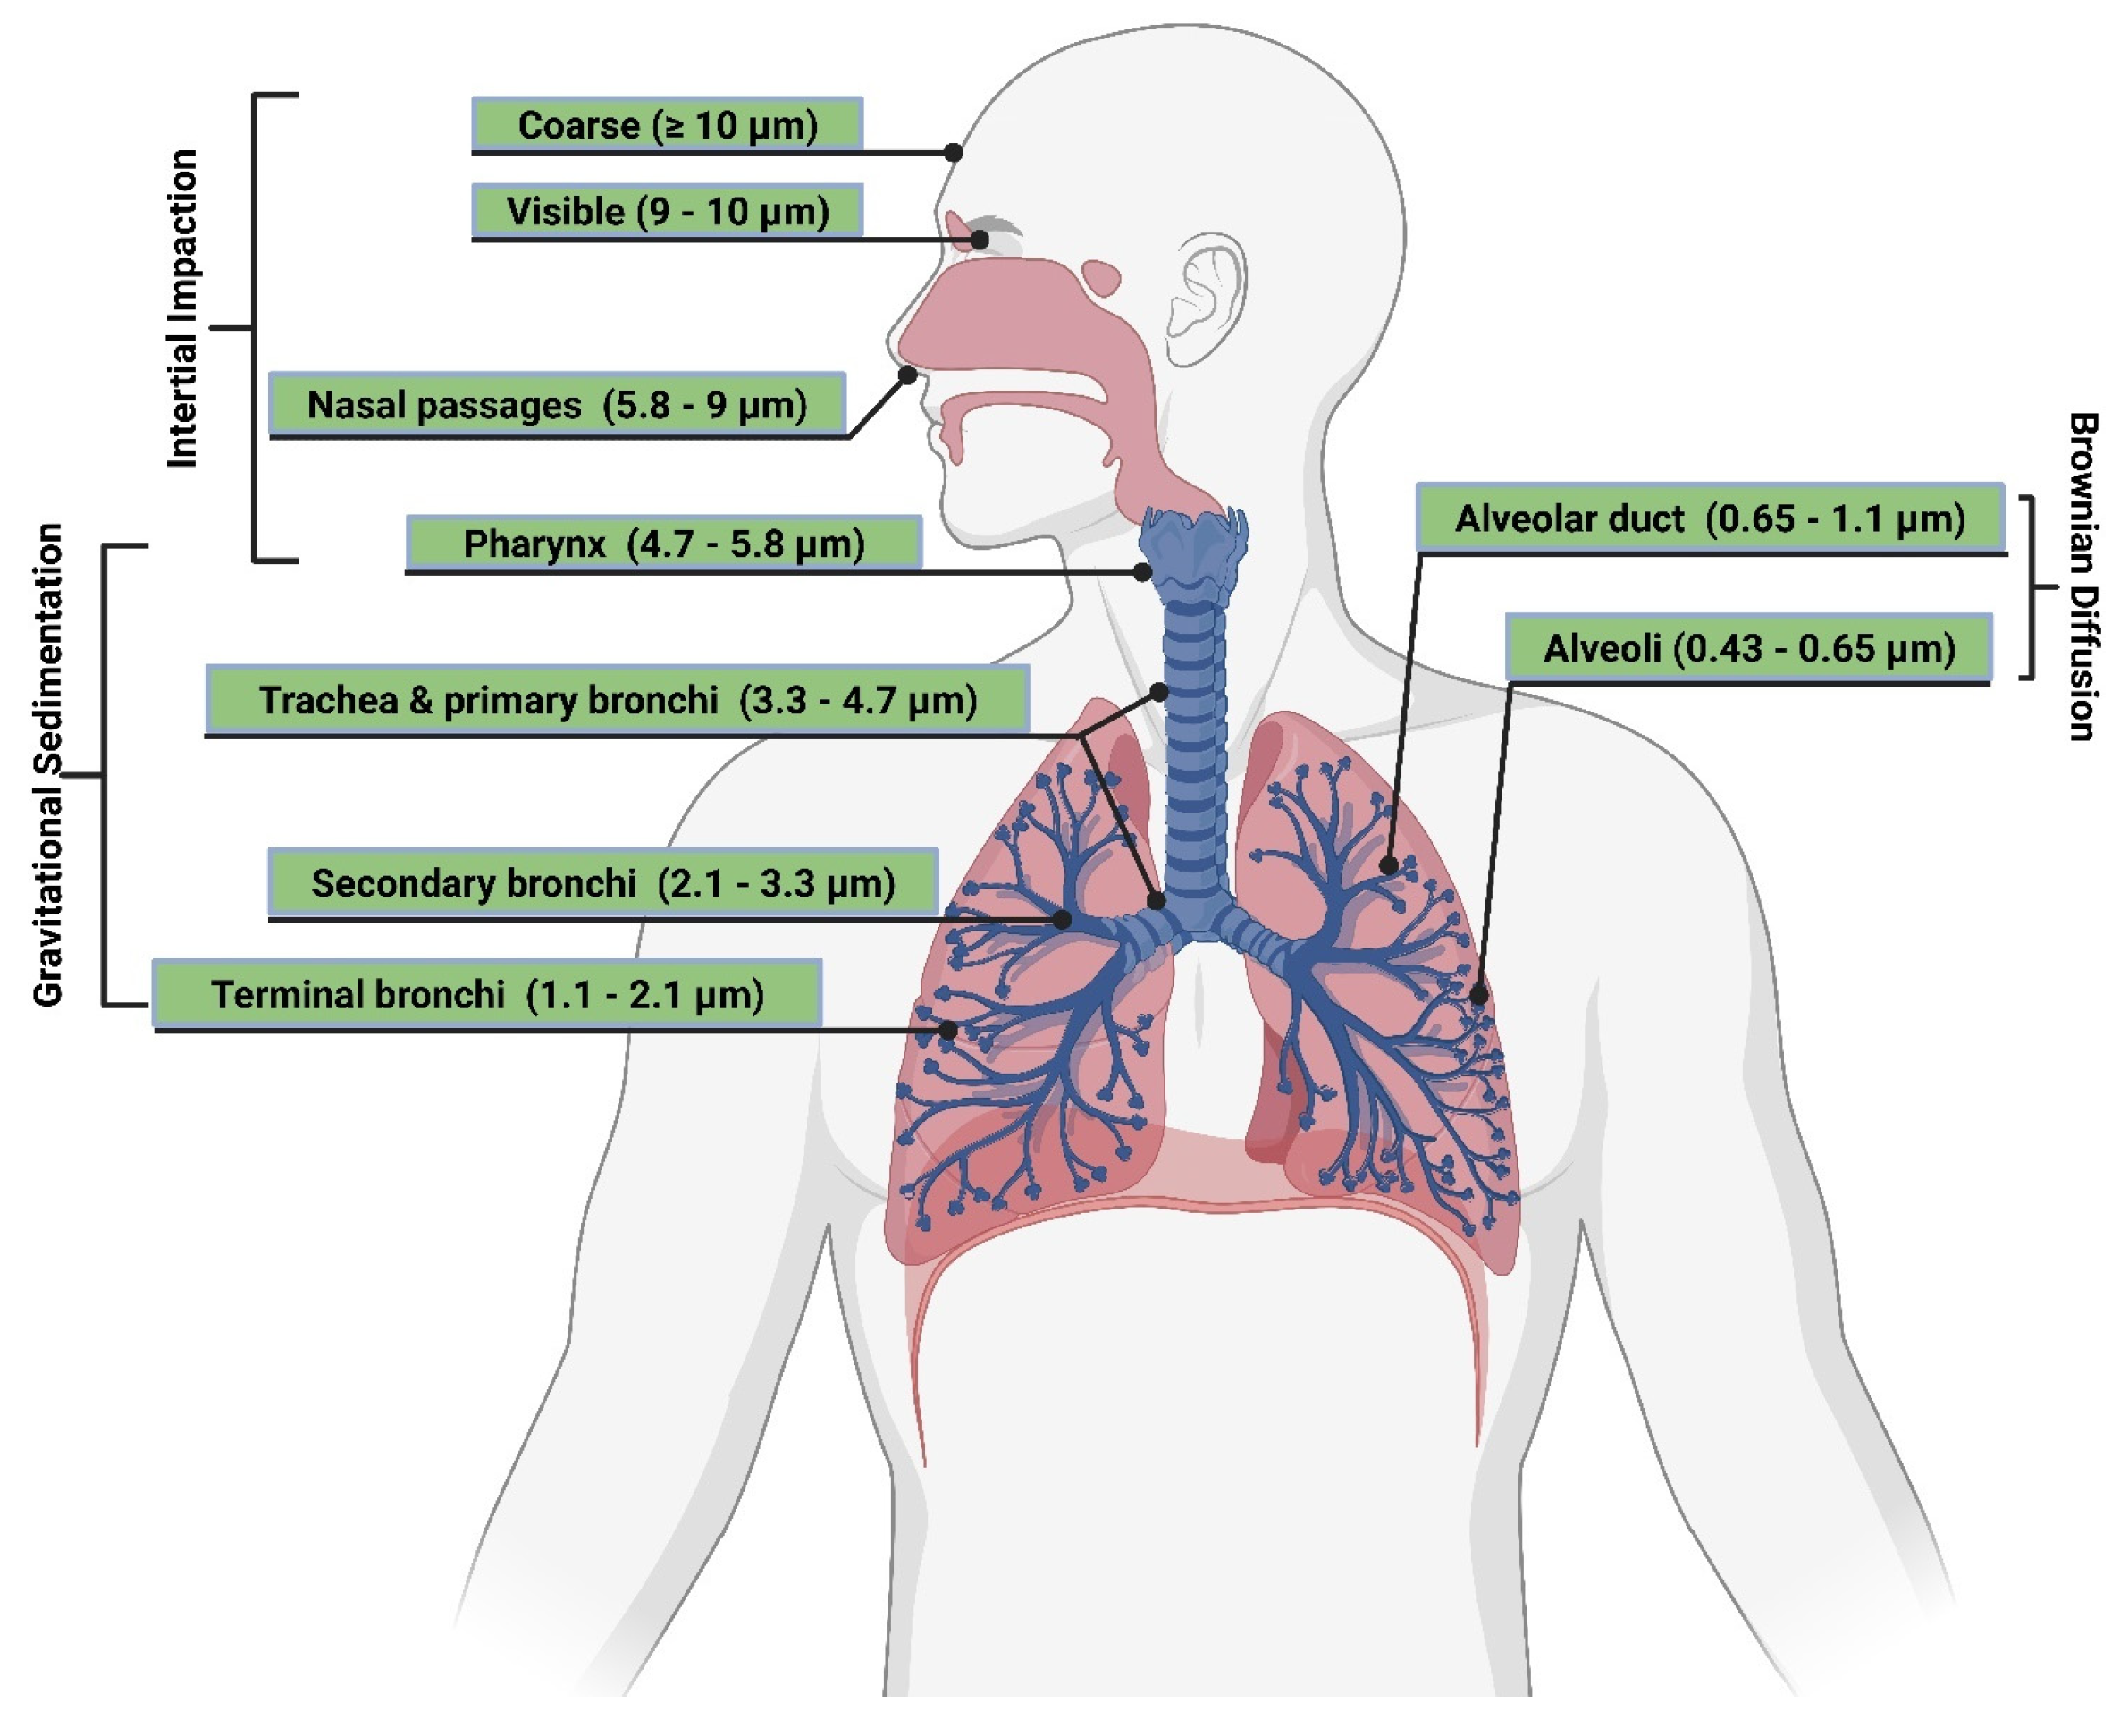

Particle Size and Deposition Pattern

- Tena, A.F.; Clarà, P.C. Deposition of inhaled particles in the lungs. Arch. Bronconeumol. (Engl. Ed.) 2012, 48, 240–246. [Google Scholar] [CrossRef]

- Darquenne, C. Deposition mechanisms. J. Aerosol Med. Pulm. Drug Deliv. 2020, 33, 181–185. [Google Scholar] [CrossRef]

- Hofmann, W. Modelling inhaled particle deposition in the human lung—A review. J Aerosol Sci. 2011, 42, 693–724. [Google Scholar] [CrossRef]